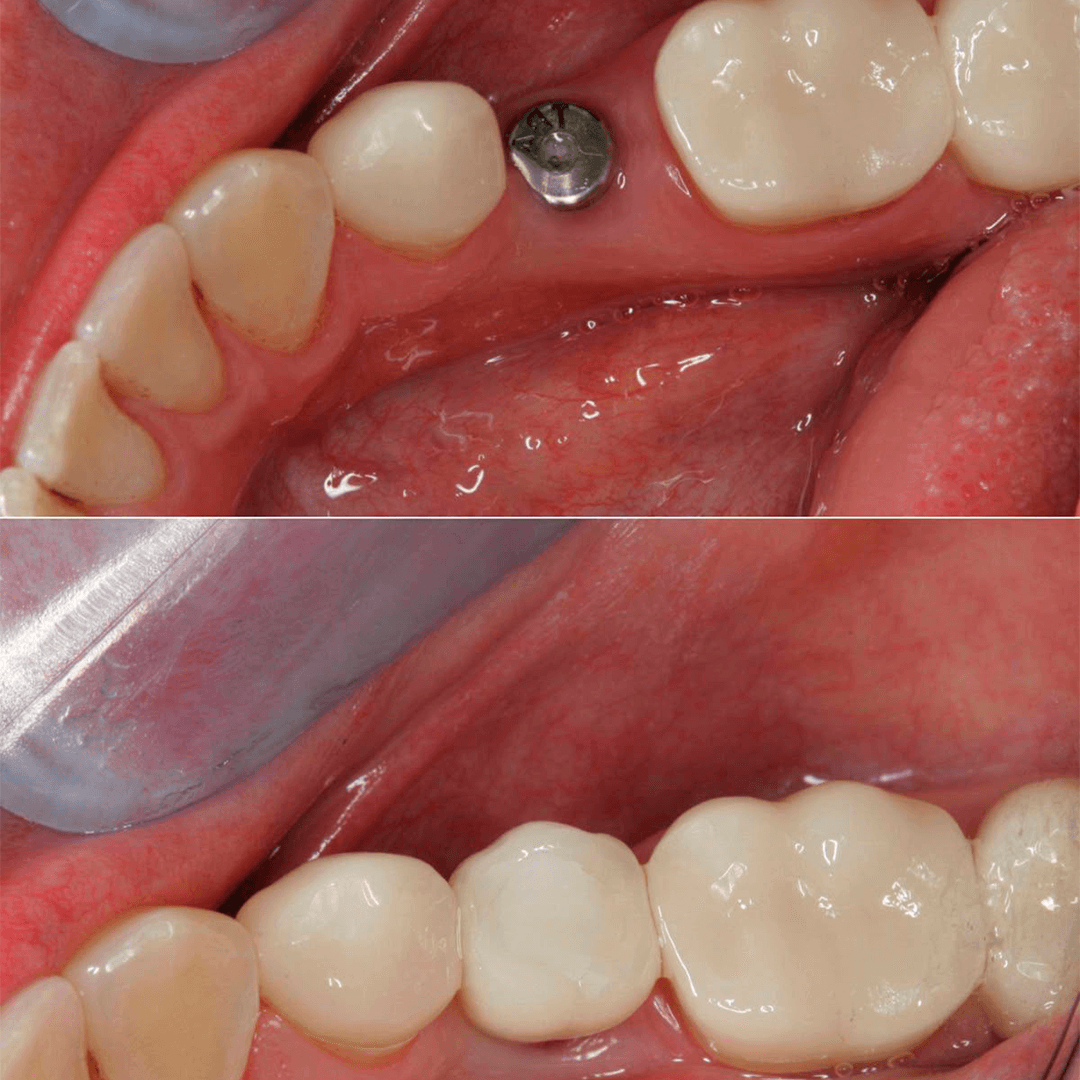

IMPLANTE

DENTAL

Un implante dental es un dispositivo médico en forma de tornillo que se inserta en el hueso maxilar para reemplazar la raíz de un diente perdido, funcionando como un anclaje para un diente artificial (corona).